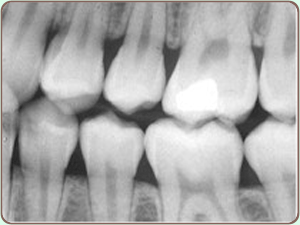

Digital X-Ray

Digital x-rays are computer-generated images. These images require up to 90% less radiation than conventional x-rays. Instead of using the traditional silver-oxide x-ray film that must be developed and fixed using caustic and environmentally damaging chemicals. Digital x-rays take pictures via a storage phosphor screen and through the use of a laser and computer immediately transmit a picture of the tooth to a video monitor in the treatment room.